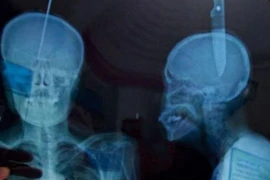

Video: Kinh dị người đàn ông tự đâm dao xuyên đầu để...thở tốt hơn

Yury Zhokhov, 41 tuổi, được tìm thấy quỳ gối trên một cánh đồng với dao dài 20cm đâm xuyên đầu.